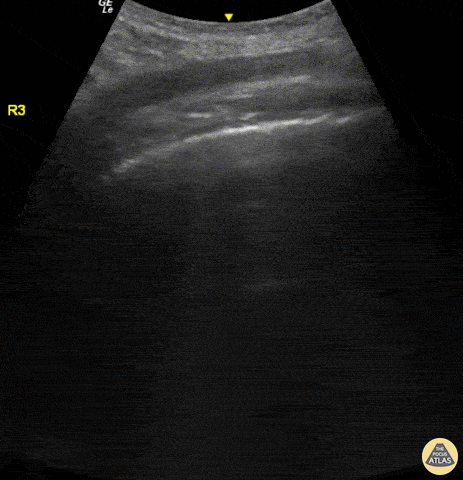

This image was taken from a 58-year-old man with cough and fever x 8 days who tested positive for SARS-CoV-2 Virus. Pictured here is a POCUS view (R3 Zone) obtained in oblique position with a curvilinear probe. Appreciate the lung sliding, regular pleural line, and alternating multiple separated B-lines and A-lines; this constellation of findings is referred to as “Light Beam Sign”. Renato Tambelli, Emergency Physician, Hospital das Clínicas de Marília, Brazil @R_Tambelli / @JediPocus